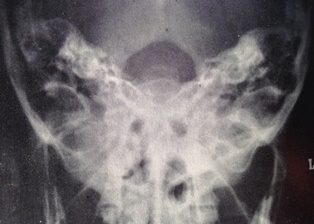

By the 1920s, radiology was becoming recognised as a distinct medical speciality. In the 1930s there was a gradual standardisation of projections which culminated in the publication of Positioning in Radiography by Kitty Clark in 1939, which remains in print today.

It was all about the position. We could see if there was something wrong with my head if I put it in the same position as yours.

Apparently it was one of Francis Bacon’s favourite text books.[x]